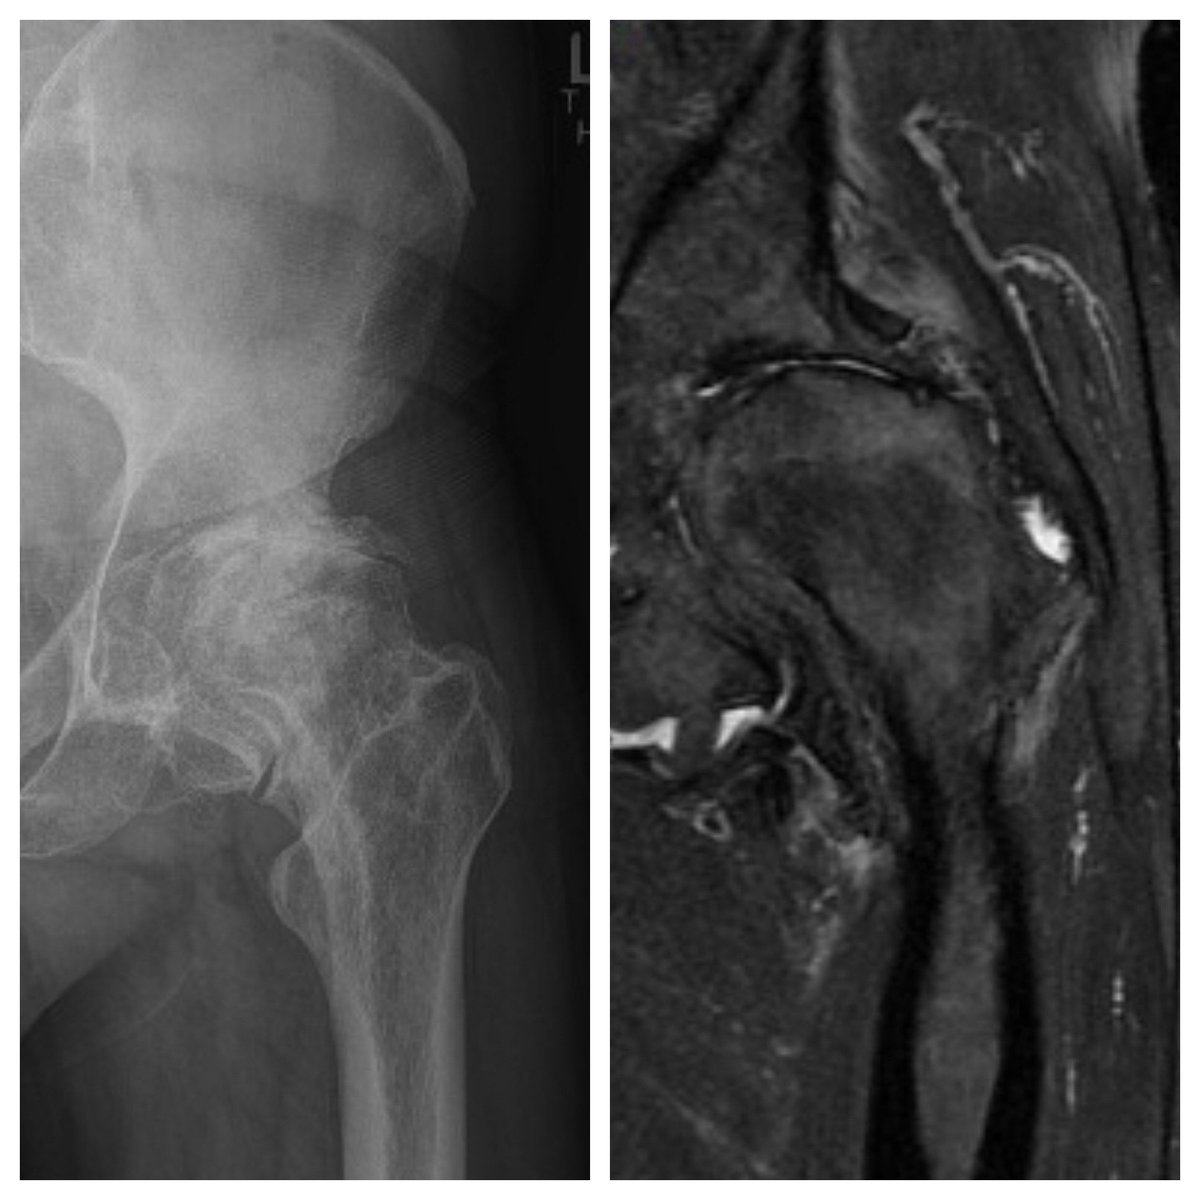

@DrBryanSaltzman @orthotraumamd @orthobullets @VaniSabesanMD @JSanchezSotelo @RachelFrankMD @MarkFrankleMD @shoulderMD I agree with Dr Saltzman. This is a preservable joint in a young active individual. Tuberoplasty or spacer would be my choice.